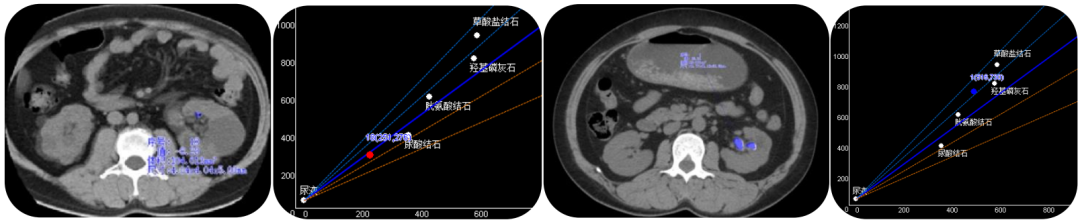

泌尿系结石智能检测

智能结石检测,可一键实现泌尿系结石的智能识别、成分分析及体积测量等分析,可检测小至1mm以下结石,检测结果一键染色2D/3D同步显示,辅助医生选择最佳治疗方案,对临床尿酸、非尿酸结石的临床治疗具有重要价值以及术前评估、疾病预防起着关键作用。